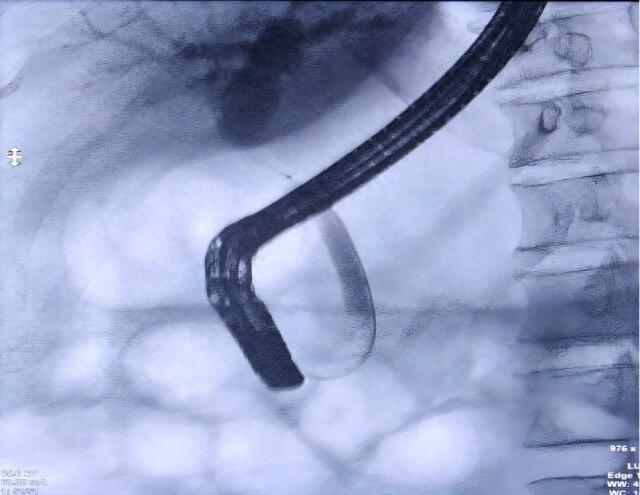

专家团队达成共识:病变部位不能排除为恶性肿瘤所致,应立即为患者实施胆道子镜检查+组织活检,明确病变性质后再制定个体化治疗方案,如果为良性病变,内镜治疗即可。通过子镜观察到患者胆总管上段存在一处长约1cm的狭窄并增厚胆管壁,并在病变部位精准钳取3块组织样本。果然,病理报告提示腺癌,这一结果证实了专家团队的初步判断。拿到诊断报告后,患者及家属陷入了悲痛之中,但罗宏武主任团队及时给予了心理疏导与信心鼓励,专家们的专业解读与暖心安慰,让患者及家属重新燃起了希望。

据中南大学湘雅三医院相关负责人介绍,医院肝胆胰外科一病区致力于肝胆胰系统疾病的临床诊疗工作,在微创外科治疗、内镜技术应用及肝硬化门静脉高压症的规范化综合治疗方面形成了显著特色。该团队常规开展胆道子镜检查、经内镜逆行胰胆管造影术(ERCP)、超声内镜(EUS)等复杂操作,在国内内镜诊疗领域处于领先地位,为胆管狭窄、胆道结石及胆胰肿瘤等疾病患者提供精准诊断与治疗。